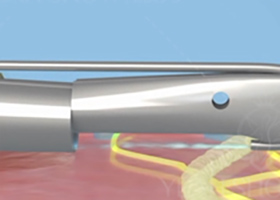

principle and development of water knife technology水刀技术通过独有组织细胞分离技术精准定位大汗腺,由发丝孔径大小的喷嘴喷射超高音速可调控的高压水流,系统采用了文丘里效应,通过无菌生理盐水水流粉碎、回吸异常大汗腺,同步实现安全便捷,术后创口自然美观,30分钟左右快速祛臭。

Break away from traditional treatment根据患者腋下的弧度选择适合患者最佳角度的手柄刀头量身定制祛臭专属方案。